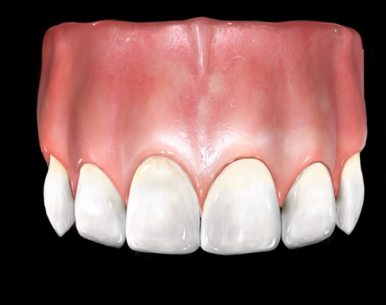

이렇게 전 후 사진비교해보니

브릿지를 하고 훨씬 나아졌습니다.

임플란트 할때보다 빠르게 진행되었고

뼈이식도 안해도 되었으며

환자분도 굉장히 만족하셔서 수정없이 진행하였고

다른 충치 앞니도 꼭 저희 치과에서 라미네이트 하겠다고 하셨습니다.